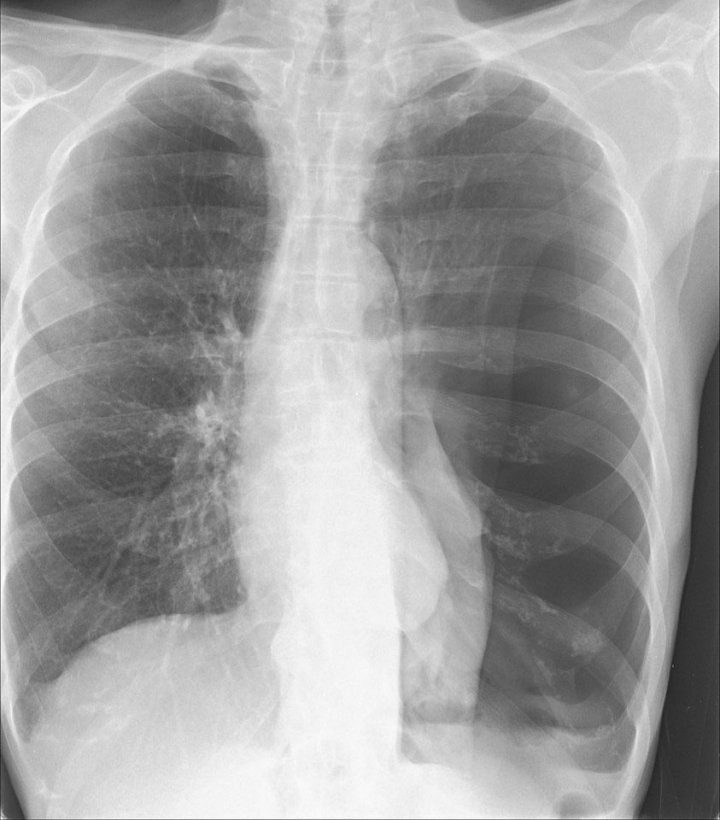

Chest X-ray showing collapsed lung, or pneumothorax.

Image courtesy of Rachael Callcut, MD